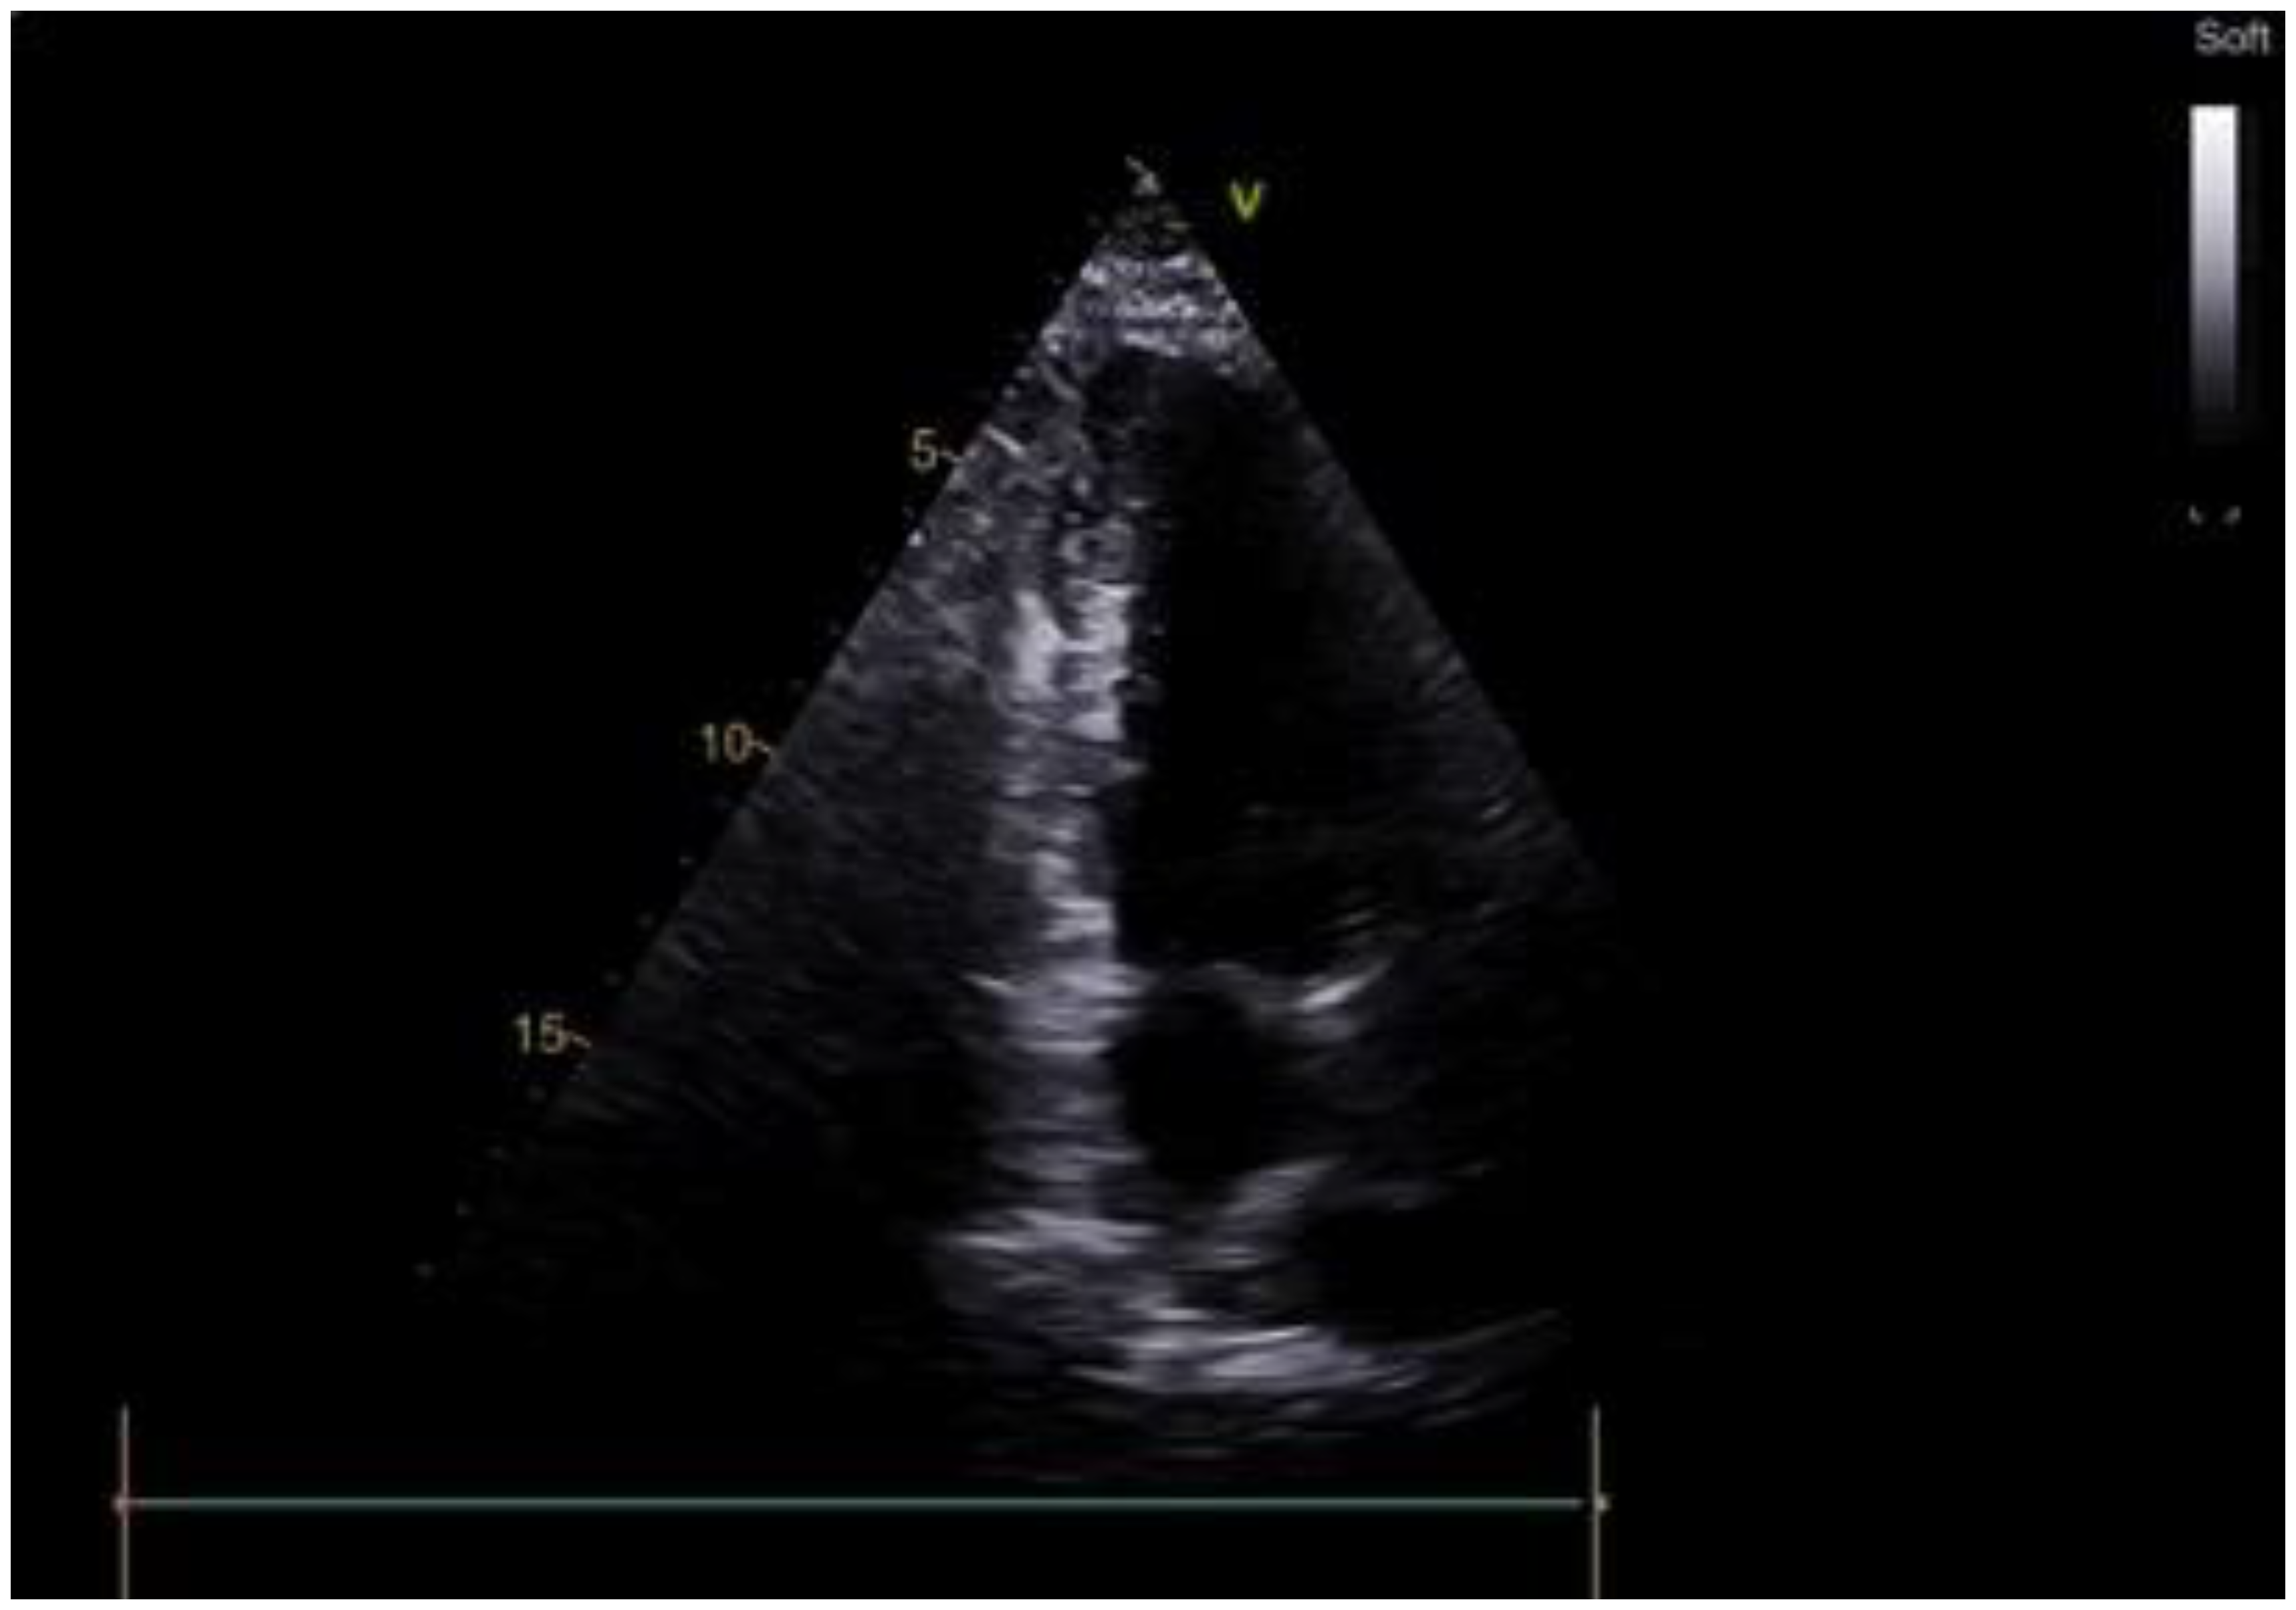

3. Results